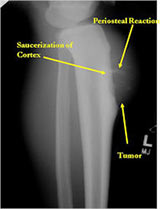

Radiographic imaging is used to help form a diagnosis. These include X-Ray, MRI, CT and Bone Scans.

An example of an X-Ray is shown.